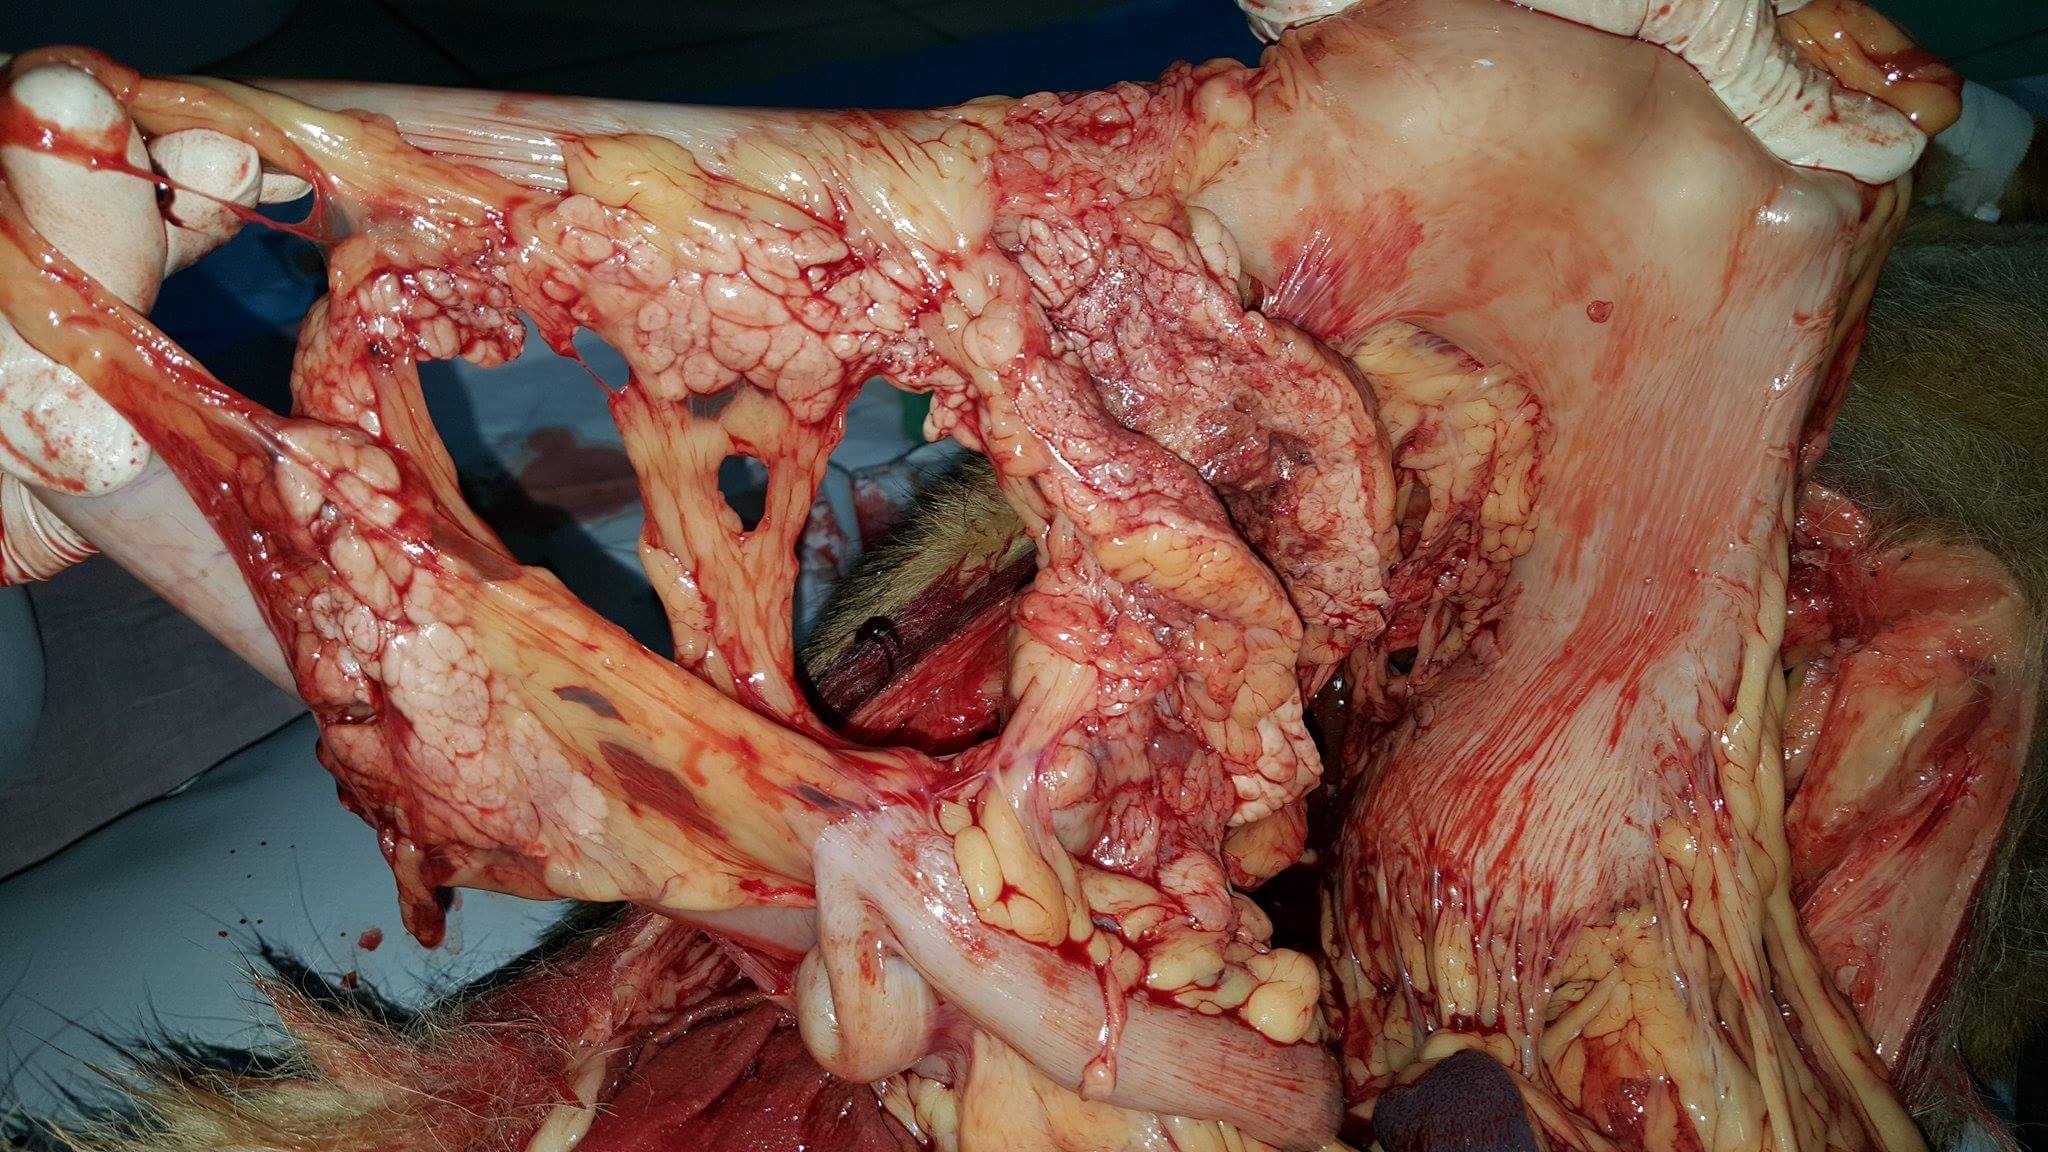

W USG płyn w j. brzusznej w dużej ilości, decyzja o eutanazji, sekcja wykazała: krwotok z guzów wątroby

zmianę obejmującą trzon i plat lewy trzustki- twardą, litą z obszarem martwicy w centrum, widać na zdjęciu brązowawy obszar we wnętrzu przekrojonego guza